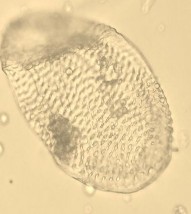

Soi dưới kính hiển vi tìm thấy các cấu tử như sau: Nhiều hạt tinh bột hình chuông, hình đa giác, nằm riêng lẻ, hạt tinh bột kép 2, 3, 4 hay tụ tập thành khối. Tinh thể calci oxalat hình khối. Nhiều mảnh mạch vạch có khoang rộng, mạch điểm, mạch mạng, lông che chở (Hình 4.8).

Nhận xét: Kết quả soi bột rễ Đinh lăng cho thấy có nhiều cấu tử được tìm thấy tương tự giống trong miêu tả của Dược Điển Việt Nam IV như: Tinh bột, mảng mạch mạng, mạch vạch. Ngoài ra còn tìm thấy các cấu tử khác như: Mạch điểm, tinh thể calci oxalate hình khối, lông che chở mà Dược Điển Việt Nam IV chưa đề cập

Mạch vạch |

Mạch mạng | |

Mạch điểm |

Tinh thể cacli oxalat hình khối |

Hạt tinh bột |

Hình 4.7. Soi bột rễ Đinh Lăng